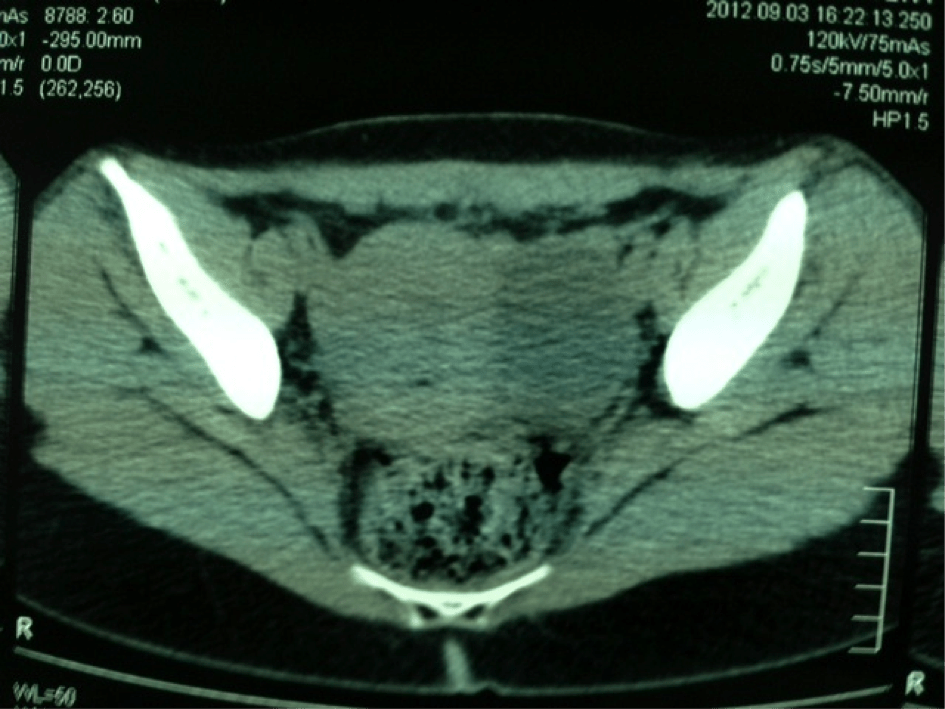

Ovaire Tératome bénin bilatéral (kyste dermoïde) Échographie